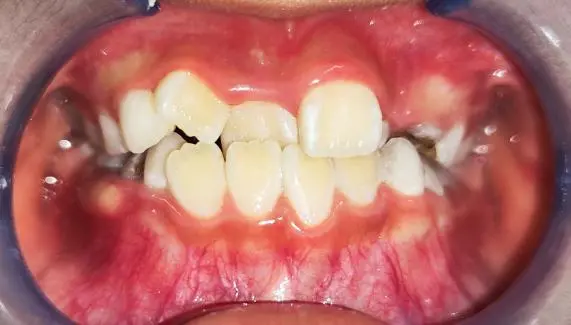

矫治前

经过医生的检查和拍片分析,诊断出小酒的个别牙反颌,上下颌牙弓狭窄、牙列拥挤,同时还有轻度的上颌骨发育不足和下颌骨发育过度。经过与杨妈妈的沟通,决定为小酒制作上颌扩弓+舌簧的活动矫治器进行替牙列期的早期矫治,将牙弓扩展到适宜宽度的同时能缓解一部分牙列拥挤的问题,配合舌簧解除个别前牙反颌。小酒的颧骨较平坦,经过医生的美学考虑和与家长的商议,决定不进行上颌前方牵引,避免造成外貌凸嘴的错觉。